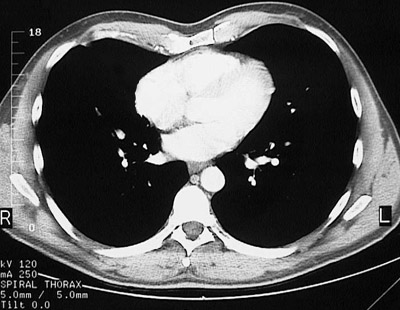

[T9] This is a normal chest CT scan demonstrating the right lung and left lung and pectoralis major muscle and right atrium and right ventricle and left atrium and left ventricle and sternum and descending aorta and azygous vein and esophagus and serratus anterior muscle and latissimus dorsi muscle and scapula and trapezius muscle and sacrospinalis muscle and transversospinal muscle in the upper chest.